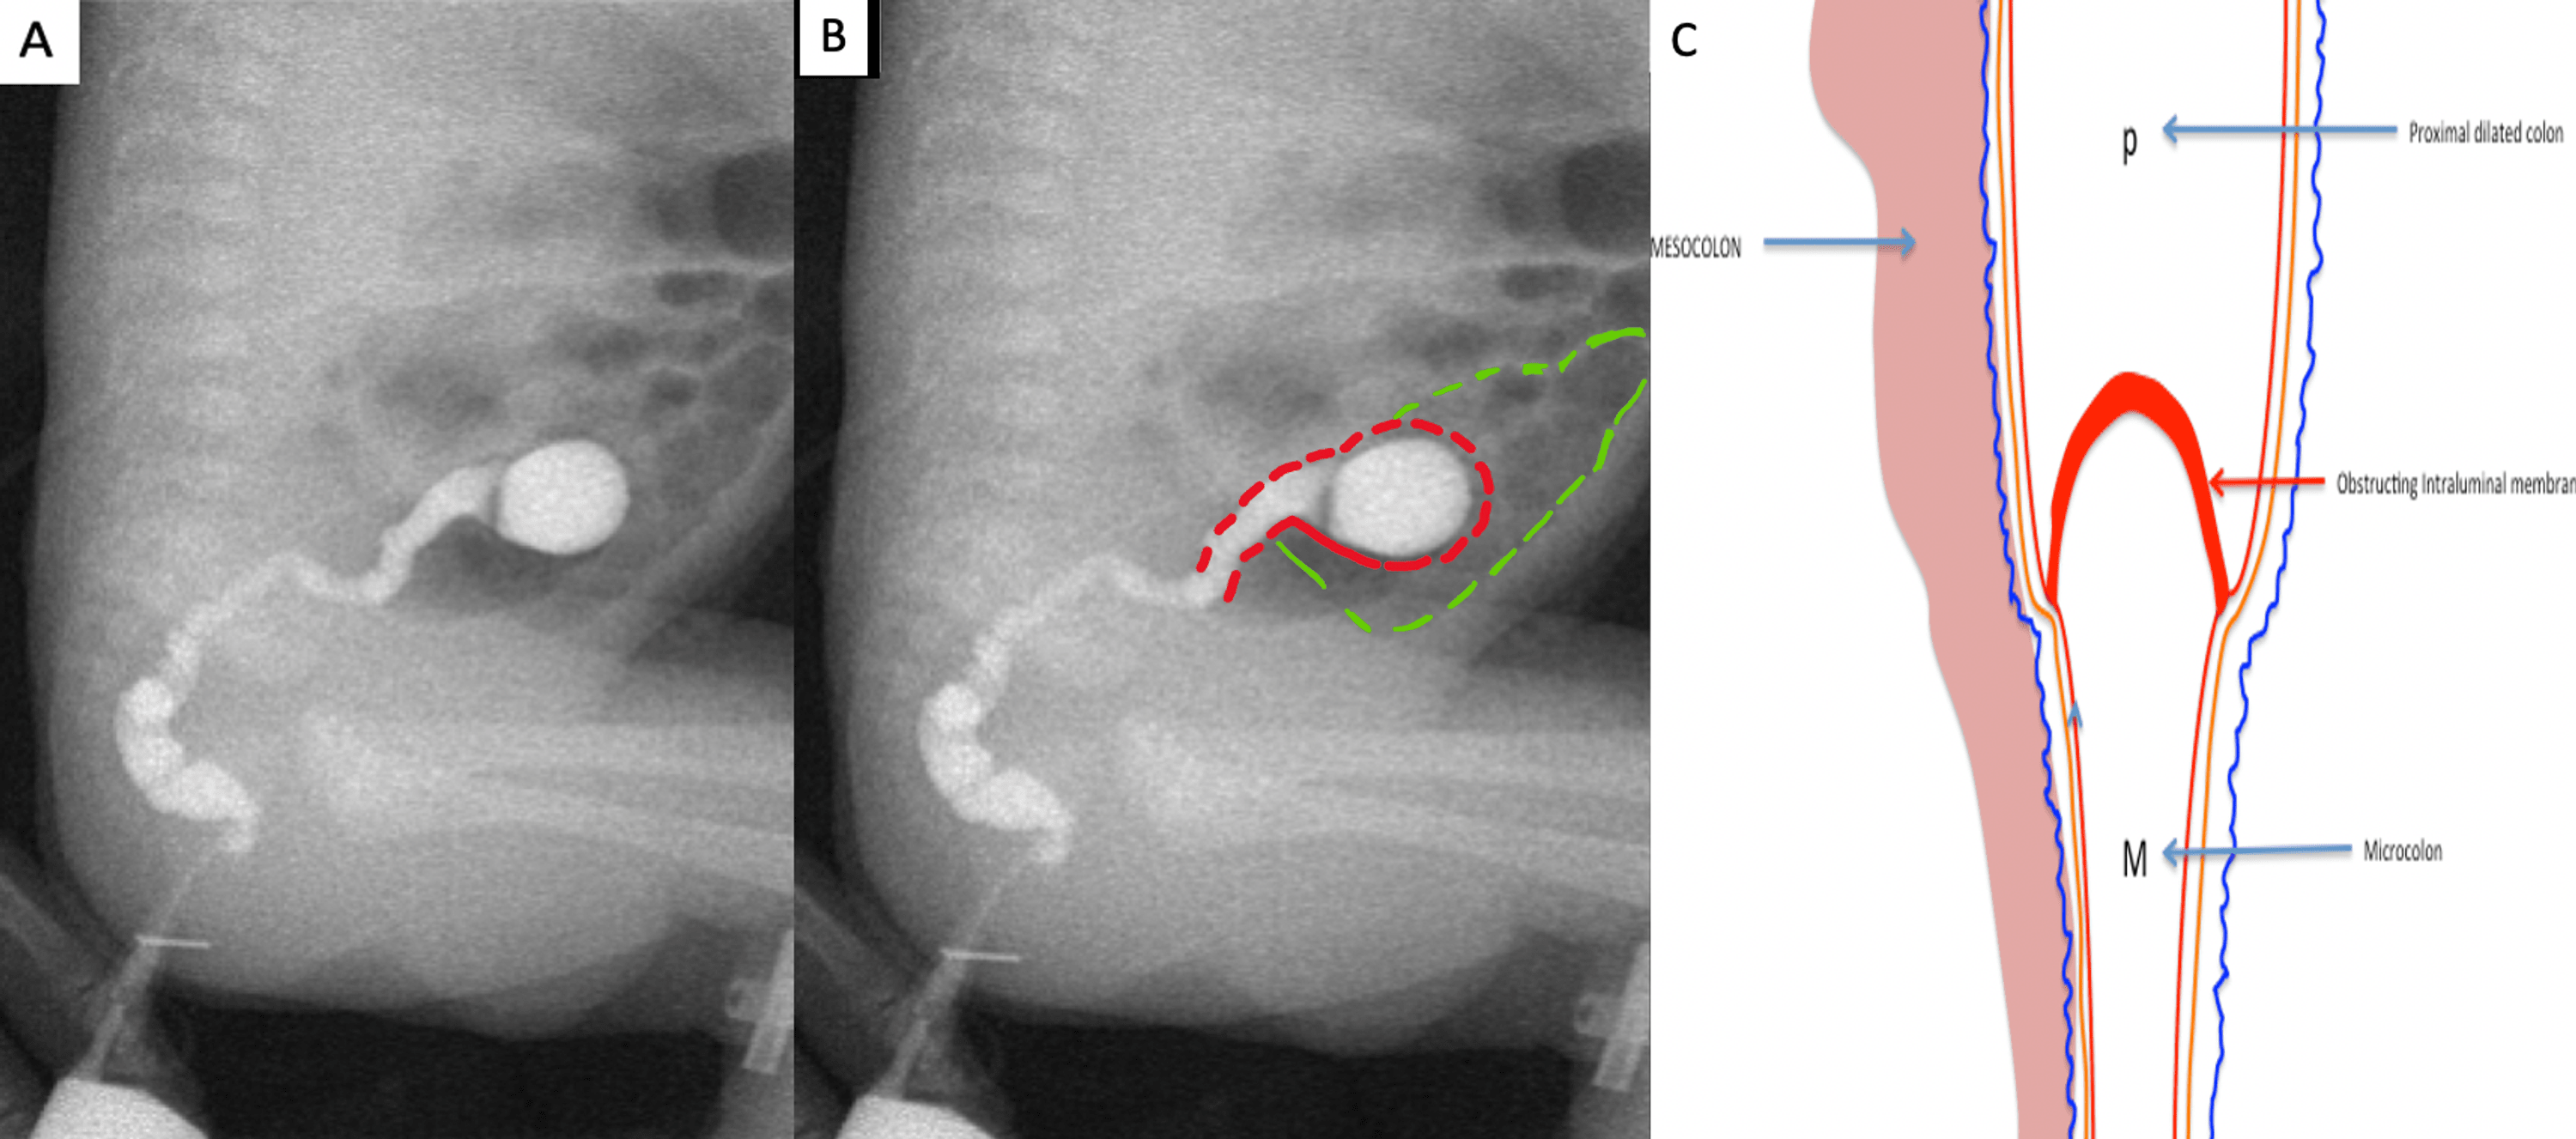

Barium meal shows dilated duodenum proximal to the web and multiple Windsock Radiology The windsock sign is a typical appearance of a d uodenal web (intraluminal duodenal diverticulum) on upper gastrointestinal contrast series which consists of an. A pathognomonic sign of internal duodenal diverticulum shankarlogarajah, maitham a.moslim, d. The “windsock sign” refers to the appearance of the intraluminal duodenal diverticulum on images from upper gastrointestinal barium series , but it is similar at. Windsock Radiology.